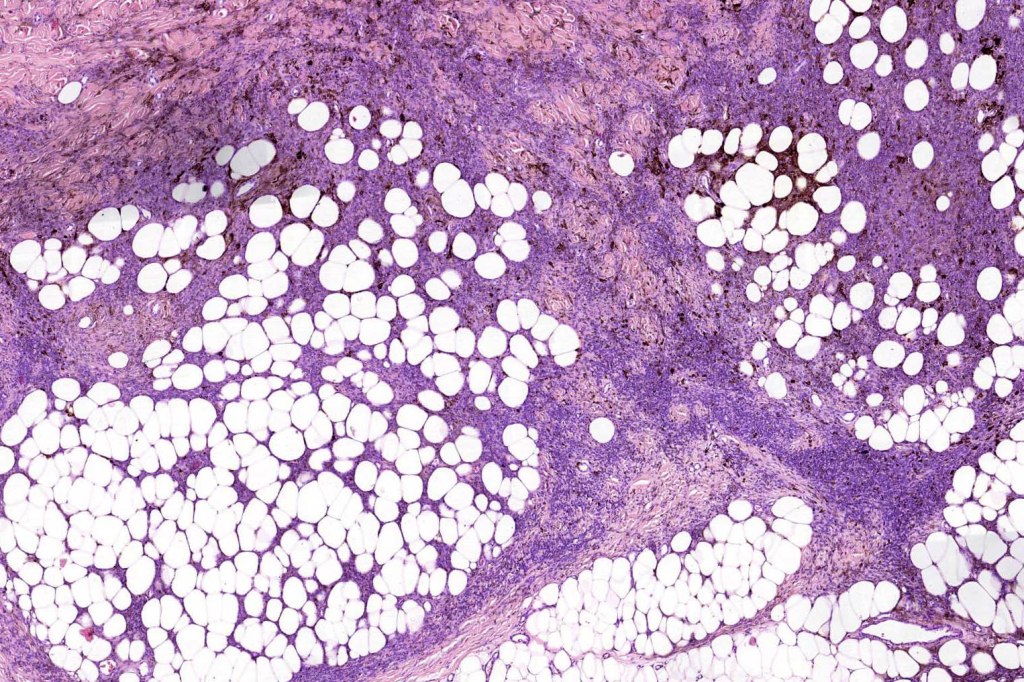

Combined congenital & blue nevus (same case as the clinical photographs coursty of Dr. Antonina Kalmykova